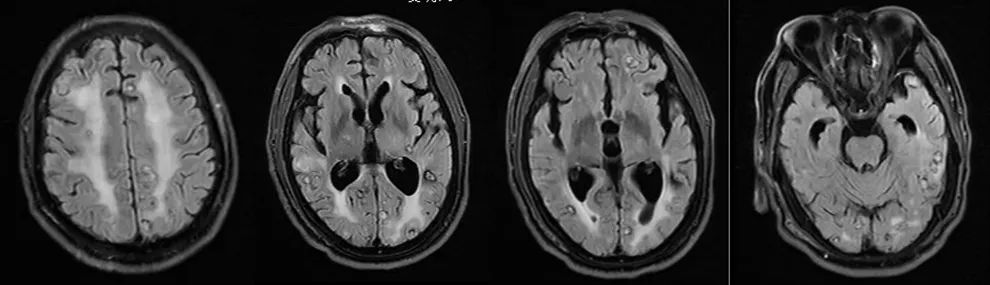

2024年9月,张先生因言语混乱、行走不稳来济宁市第一人民医院就诊,经全面检查确诊为右肺腺癌(IV期)伴多发脑转移,基因检测显示无敏感突变,影像学检查显示颅内如繁星般散布着多个转移灶,病情危急。肿瘤科陈卫东教授团队立即组织多学科会诊,制定个体化治疗方案。先行全脑放疗控制颅内病灶,同步给予脱水降颅压治疗,密切监测神经系统症状变化。放疗结束后,患者出现预期中的放射性脑水肿,一度陷入昏迷,医疗团队迅速调整方案,加强降颅内压治疗,同时给予营养支持、预防癫痫等治疗并加强卧床护理。

在医护人员的精心守护下,患者终于在昏迷3天后奇迹般苏醒,随后病情逐步稳定。目前,患者已完成后续6周期全身化疗,近期复查显示脑转移灶明显缩小,肺内病灶稳定,疾病得到有效控制。

图为:放疗前及近期颅脑MRI对比